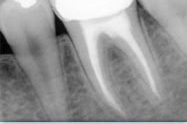

- preparazione e l’otturazione del canale;

- controllo radiografico del risultato;

- nel caso in cui ci sarà bisogno, si applica una corone dentale per sigillare e proteggere il dente.